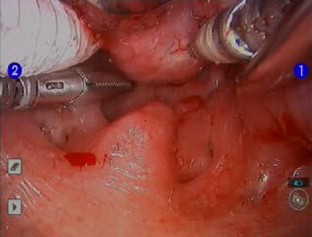

Lingual thyroid is a rare condition in which ectopic thyroid tissue is present in the base of tongue. We present a case of a 46-year-old patient with a symptomatic lingual thyroid that was successfully removed with minimal morbidity using transoral robotic surgery. The traditional treatment algorithm for lingual thyroid is reviewed. The advantages of using transoral robotic surgery to remove lingual thyroid tissue are described along with the reasons why the addition of this technique should shift treatment of lingual thyroid towards more frequent use of surgical ablation. This report is, to our knowledge, the first describing the use of transoral robotic surgery for treating lingual thyroid.

Fig. 2